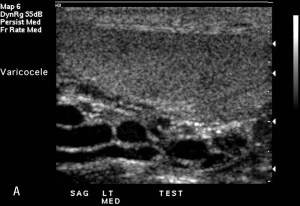

Varicocele